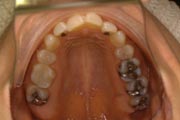

Crowding

Before